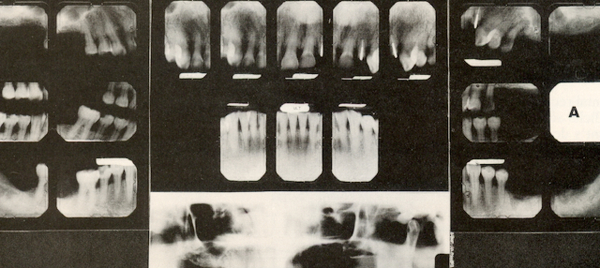

Although bite mark analysis — the practice of comparing dental impressions with a suspect’s dentition — has been allowed in criminal courts for more than 40 years, over the past two decades, the accuracy of bite mark analysis has been increasingly questioned, even by former pioneers like Miami’s Dick Souviron, who famously used it to help convict serial killer Ted Bundy in the 1970s.

In Buffalo, we met up with a married couple of dentist academics who, just a few years ago, finally took the time to conduct actual research by biting cadavers. They discovered it was all pretty much bullshit.

“When we started, we noticed that no matter where we bit or how we bit it was still going to look different, and we couldn’t predict how that was going to look, or how much distortion it was going to have. That was a basic finding that we had, that the bites simply were not predictable.”